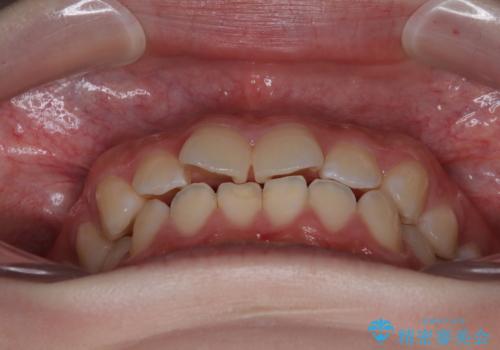

- 上下前歯部のデコボコを気にして来院された患者様です。

叢生は軽度であったため、マウスピースでもワイヤー装置でも対応可能でしたが、マウスピースを長時間使用する自信がないとのことでワイヤー装置にて矯正治療を行うこととしました。

叢生が軽度であったため、僅か半年で装置を除去することができました。